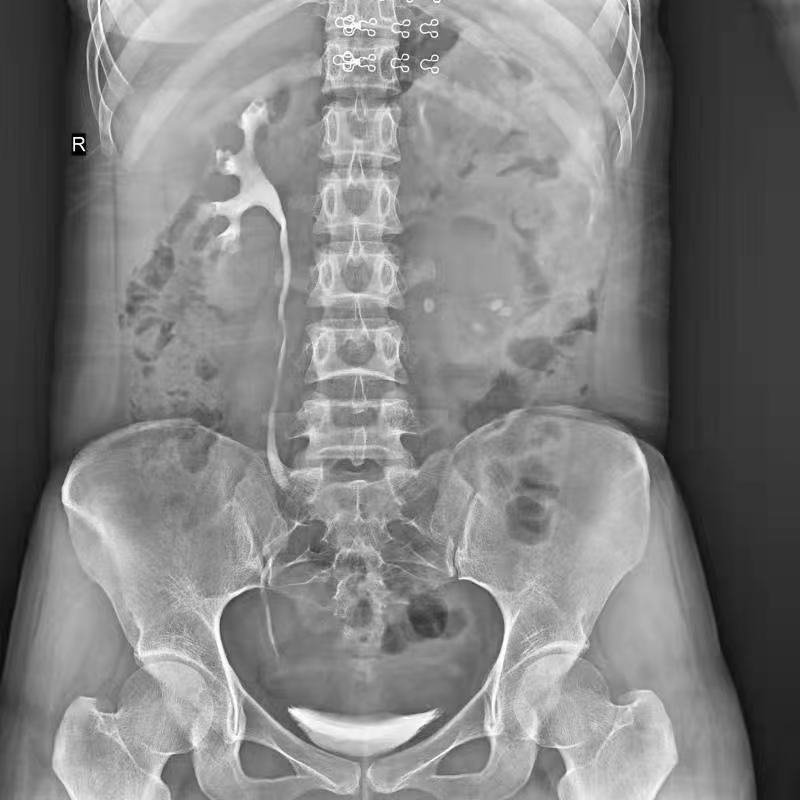

●呈現(xiàn)全下肢或全脊柱圖像

●在脊柱及下肢畸形矯正手術(shù)治療中,為術(shù)前方案制定和術(shù)后復(fù)查提供精準(zhǔn)測(cè)量

●有效解決傳統(tǒng)X光片不能一次成像問題,為患者提供更加優(yōu)質(zhì)的醫(yī)療服務(wù)